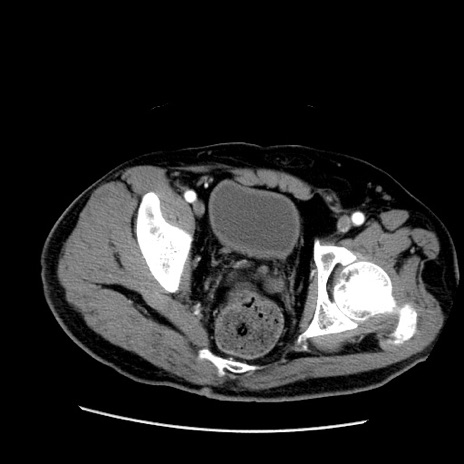

症例22(横断像)

【症例】50歳代男性

【主訴】腹痛

【現病歴】AVMからの被殻出血のため回復期リハ病棟入院中。 本日午後3時頃急に下腹部痛が出現した。

【既往歴】AVM、被殻出血、虫垂炎、高血圧

【身体所見】意識晴明、左半身不全麻痺、会話の理解は良好、36.5°C、腹部:膨隆、全体に板状硬、下腹部正中に圧痛点あり、反跳痛-、筋性防御不明、右下腹部にope scar

【データ】WBC 9400、CRP 0.06